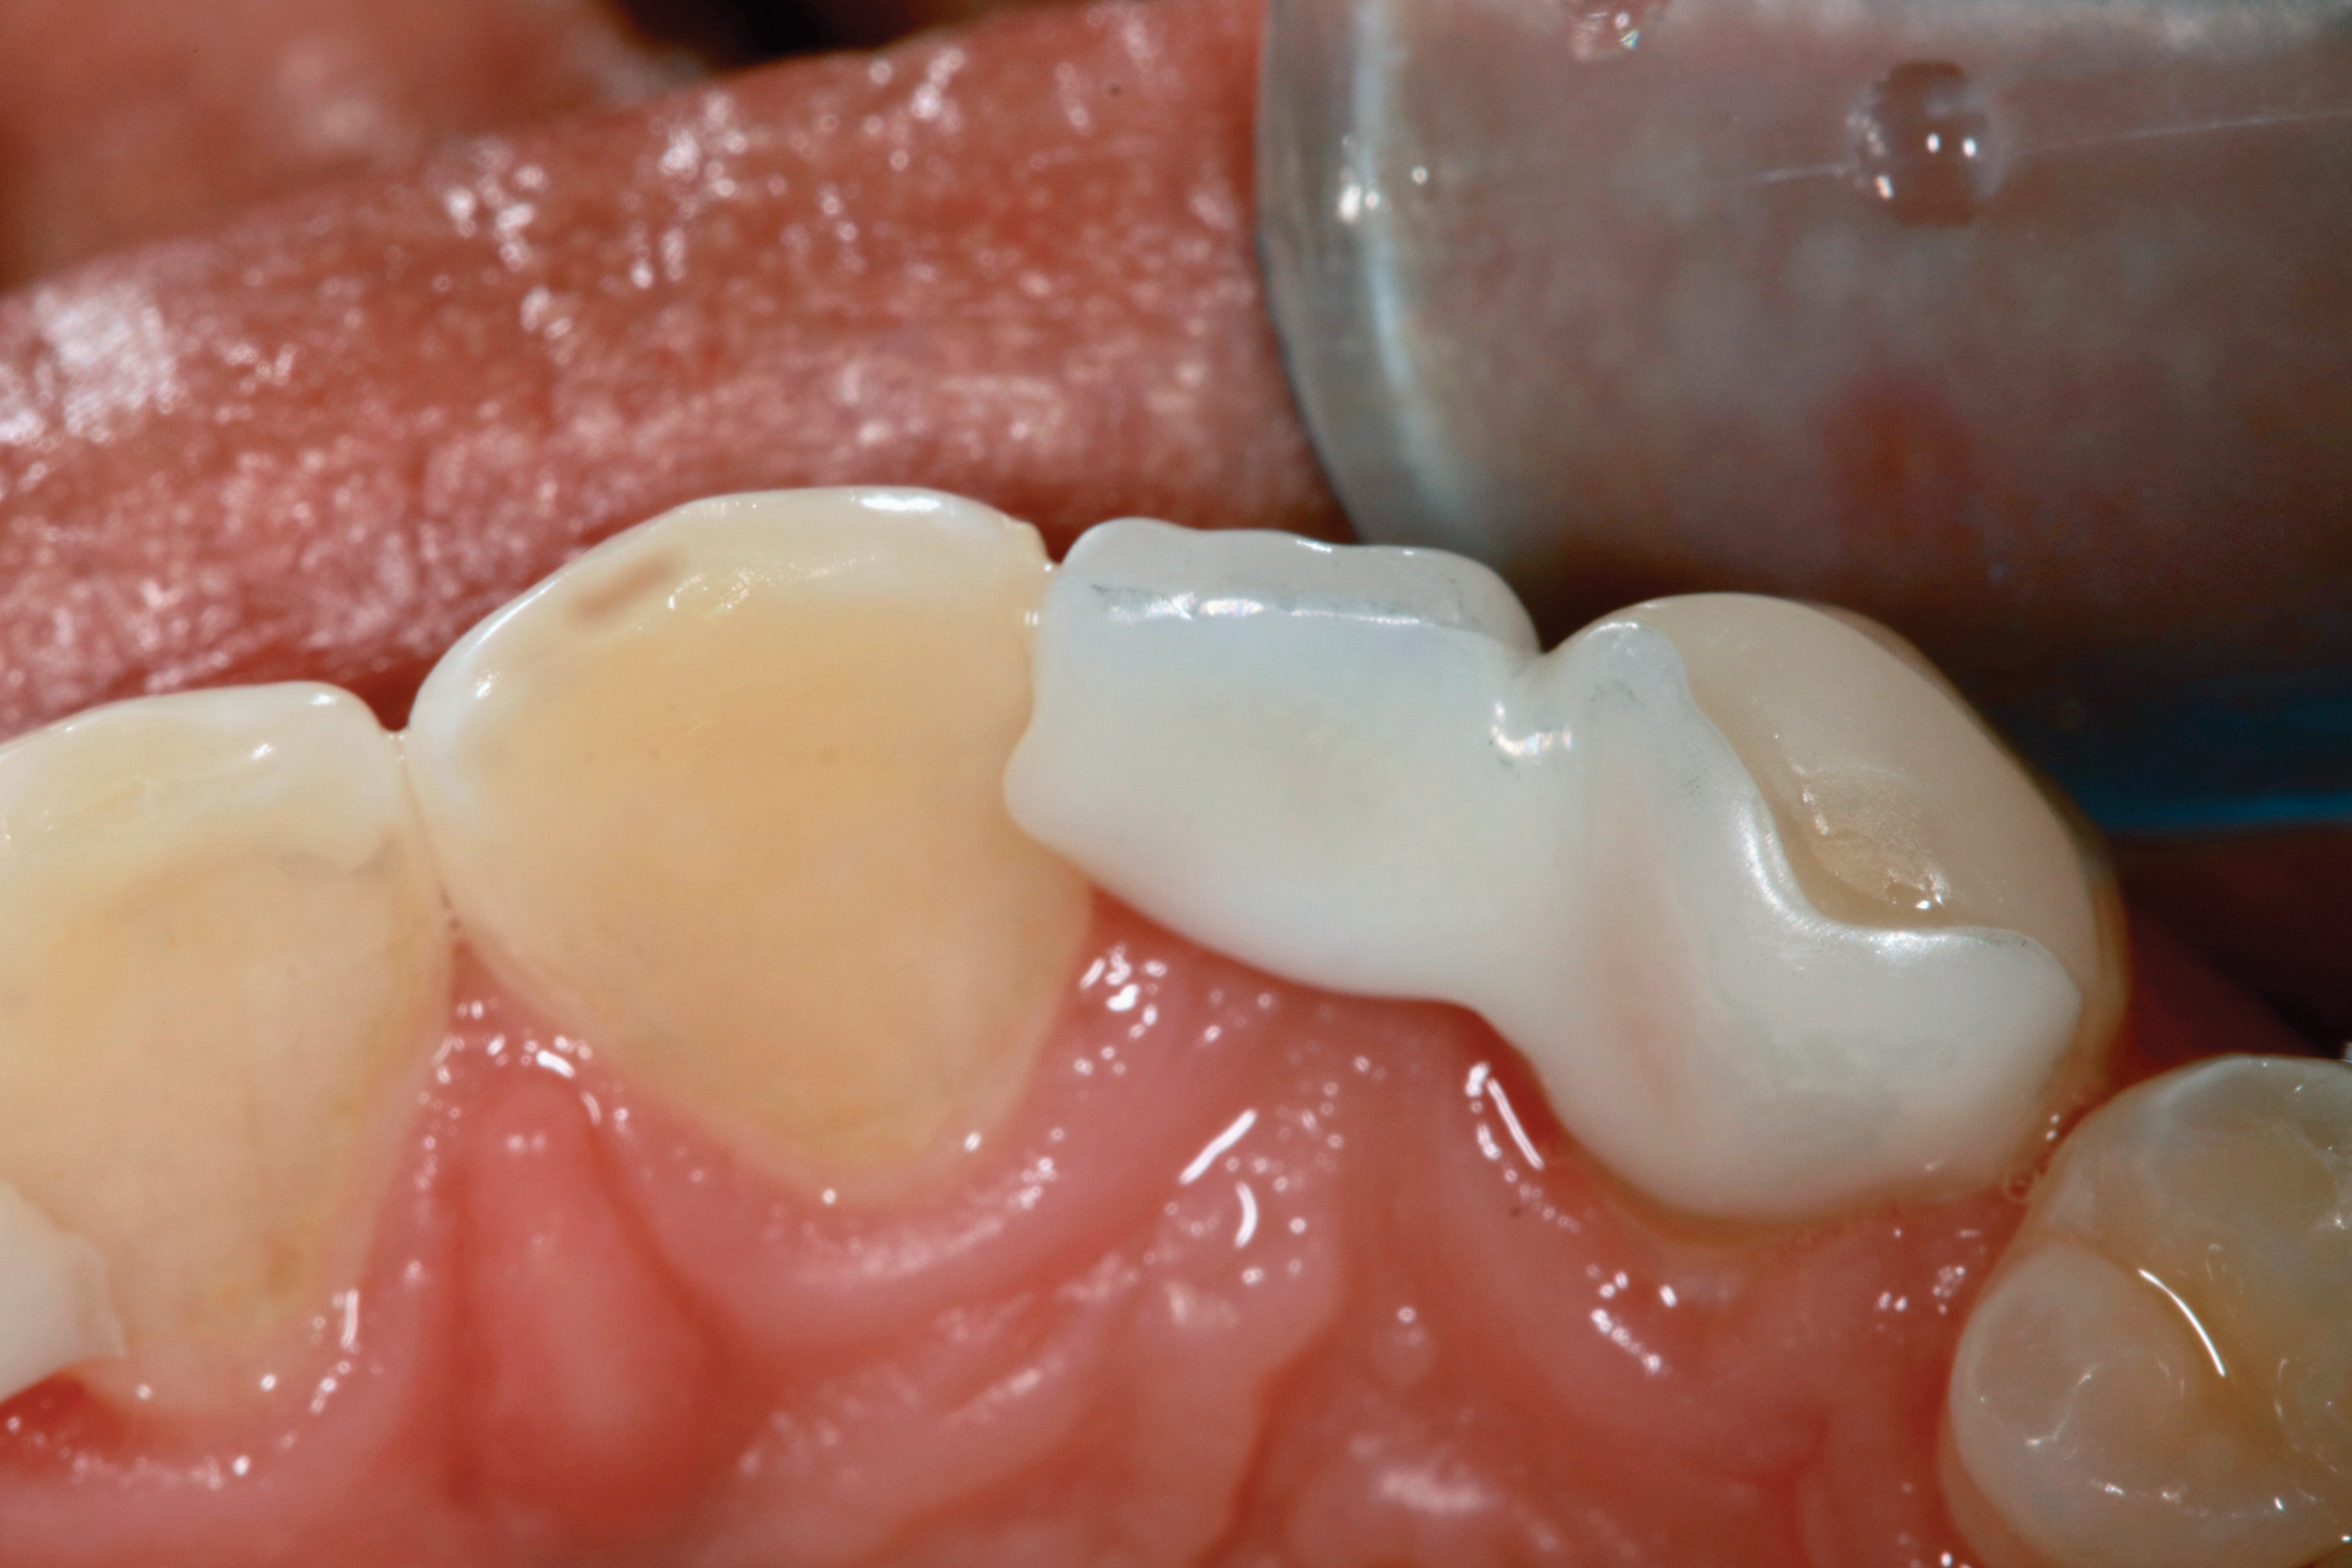

Next, the pontic must have resistance to facial displacement. This is accomplished by adding a slight extension on the pontic adjacent to an unbonded tooth; this will prevent the pontic from moving facially when loaded from the lingual (Figure 16). There should be no preparation on the unbonded tooth, nor should the extension be bonded so flossing may be easily accomplished. There must also be resistance form on the abutment, which can be best achieved with a vertical groove or box on the lateral surface of the abutment, adjacent to the edentulous site (Figure 17).29 There should be no excursive contacts on the pontic. Lastly, an evidence-based bonding protocol is essential for long-term success.

Fig 16. Occlusal view of the zirconia bonded bridge in Fig 15 at 4-year postoperative showing one wing on the canine abutment and a small anti-rotation extension from the pontic onto the distolingual surface of tooth No. 8.

Figure 16